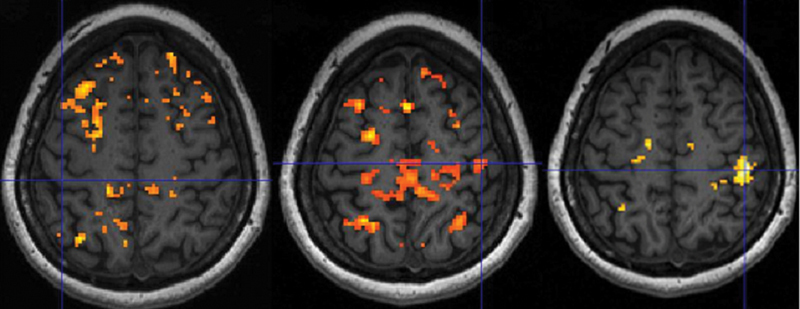

Background  Compression neuropathy, such as carpal tunnel syndrome (CTS), results in changed afferent nerve signaling, which may result in changes in somatosensory brain areas. The purpose of this study was to assess cerebral changes following unilateral CTS and to assess short-term and long-term cerebral effects of guided plasticity treatment using ipsilateral cutaneous forearm deafferentation. Methods  Twenty-four patients with mild-to-moderate unilateral CTS were randomized to treatment with anesthetic cream (EMLA) or placebo. Patient-rated outcomes were assessed using Boston CTS questionnaire and disability of arm, shoulder, and hand questionnaire (QuickDASH). Patients were assessed for tactile discrimination and dexterity. Cortical activation during sensory stimulation was evaluated with functional magnetic resonance imaging at 3T. Assessments were performed at baseline, 90 minutes, and 8 weeks after treatment. Results  Functional magnetic resonance imaging showed that sensory stimulation of the hand with CTS resulted in significantly less cortical activation in the primary somatosensory cortex (S1) than stimulation of the healthy hand. Treatment with cutaneous forearm deafferentation on the side with CTS resulted in increased cortical activation in S1 both after the initial treatment and following 8 weeks of treatment. In addition, QuickDASH and tactile discrimination showed improvement in the EMLA group over time. Conclusions  Stimulation of median nerve-innervated fingers in patients with unilateral CTS results in smaller-than-normal activation in the contralateral S1. Cutaneous forearm anesthesia on the side with CTS results in larger activation in S1, suggesting recruitment of more neurons, and a slight improvement in sensory function.

Abstract Image